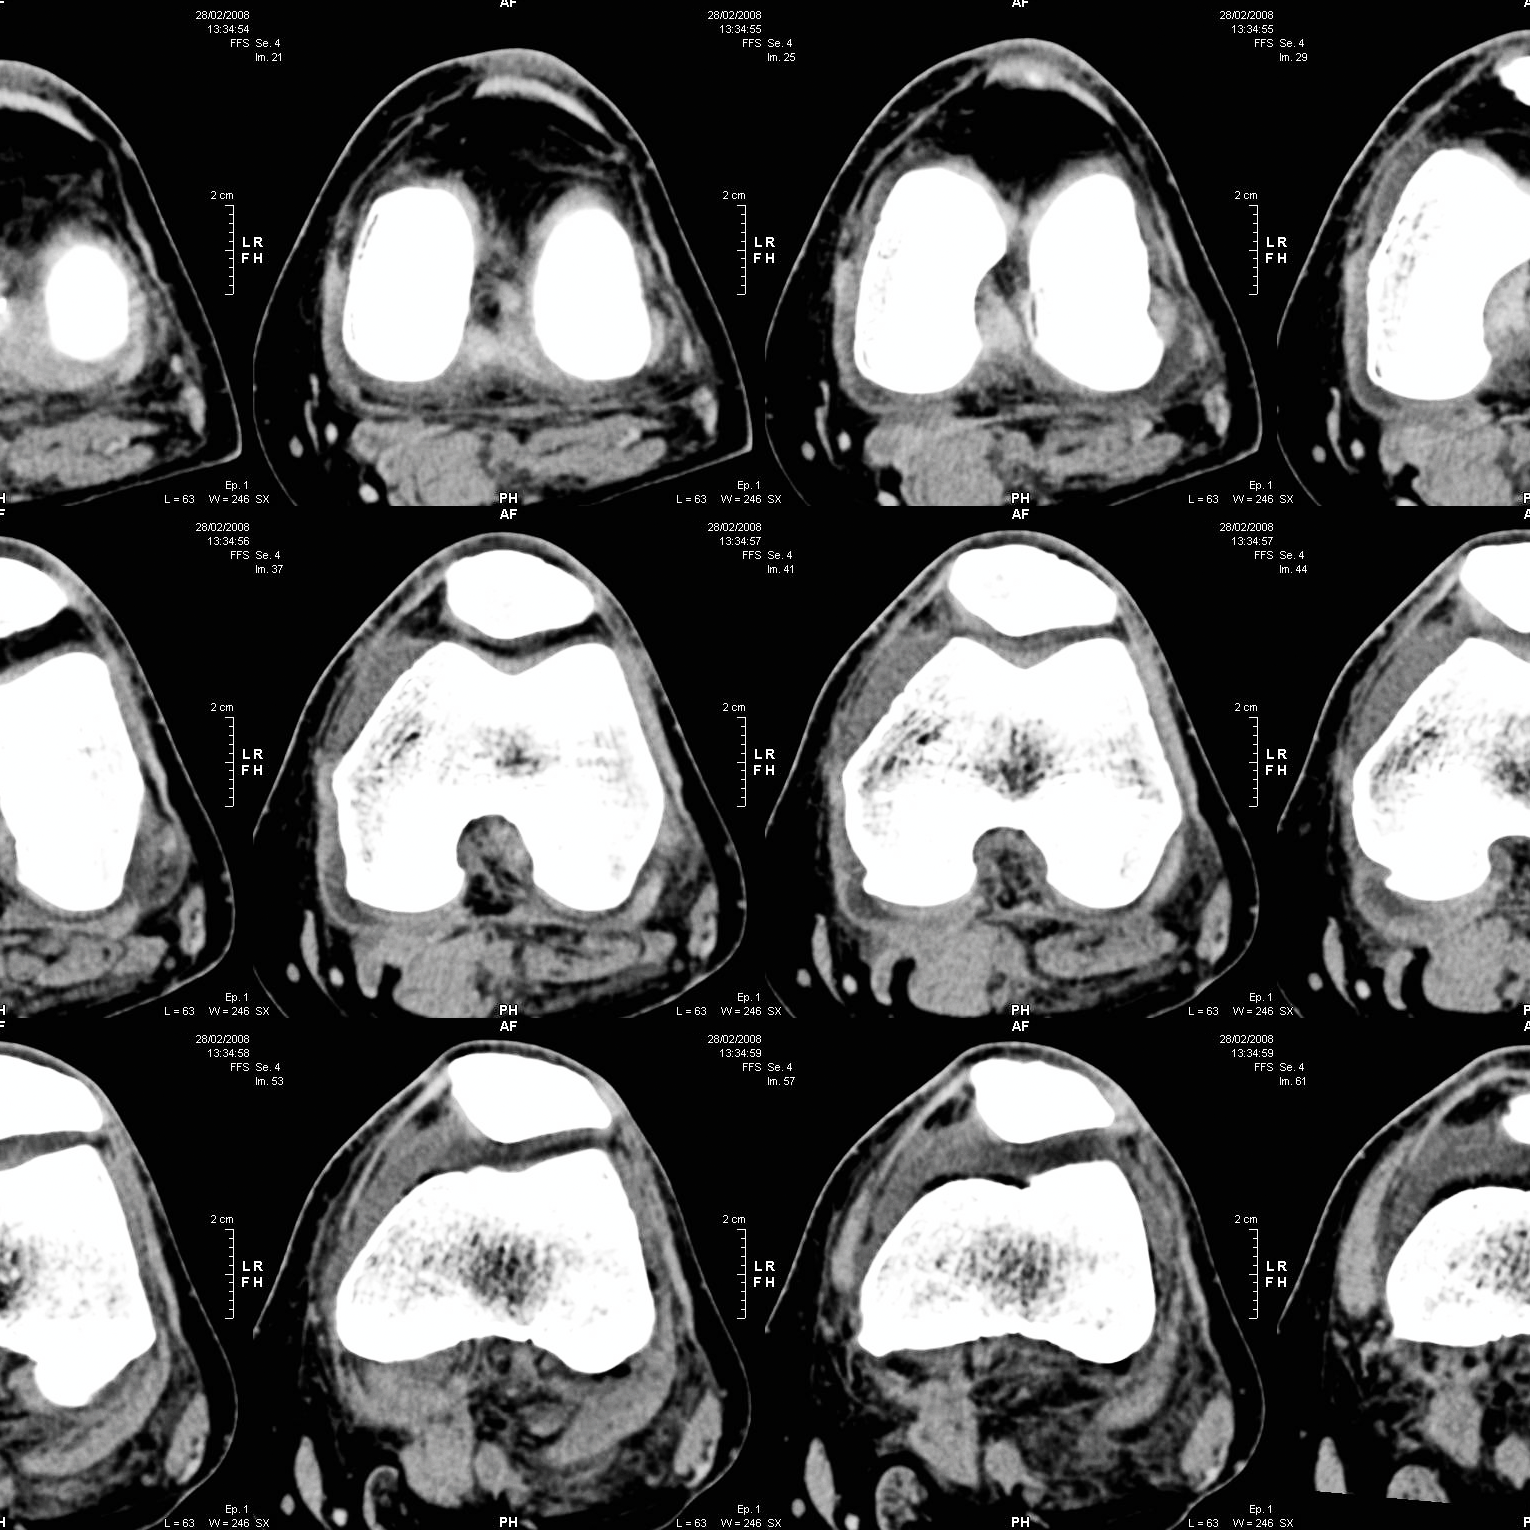

Dank CT-basierter 3D-Planung und der einzigartigen AccuStop™-Technologie ermöglicht der Stryker Mako-Roboter minimalinvasive Eingriffe, bei denen gesundes Gewebe optimal geschont und das Implantat millimetergenau positioniert wird.